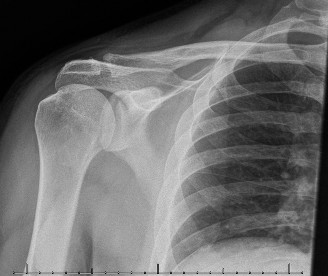

CASE 20 A 72-year-old, right-hand-dominant male with a history of type 2 diabetes, hypertension, and coronary artery disease presents to clinic for a second opinion regarding worsening left shoulder pain 8 months after undergoing a left total shoulder arthroplasty. He had an uncomplicated procedure and has had no major postoperative complications thus far; however, he has never been completely pain free since his procedure. He denies any recent trauma, fevers, chills, or drainage from the incision site. On examination, the incision sites are clean, dry, and intact, and he has mild tenderness to palpation diffusely over the left shoulder as well as decreased range of motion. Imaging is shown in Figure 2–55.

Figure 2–55

The correct answer is (C). This patient’s story of acutely worsening pain without known trauma and with a history of orthopaedic implants is suspicious for infection. Risk factors for infection include rheumatoid arthritis, diabetes mellitus, systemic lupus erythematosus, malignancy, immunosuppression, etc. The first step in this diagnosis would be CT arthrogram of the shoulder to evaluate for loosening as sign of infection. A is incorrect as, although infection is on the differential, it has not yet definitively been diagnosed and therefore an immediate irrigation and debridement would not be indicated. MRI (Choice B) might be helpful in identifying a joint effusion or bony edema/signal intensity but would not provide as useful information as synovial fluid would at this point. Choice D is incorrect because the patient must be worked up for infection before deciding on conservative